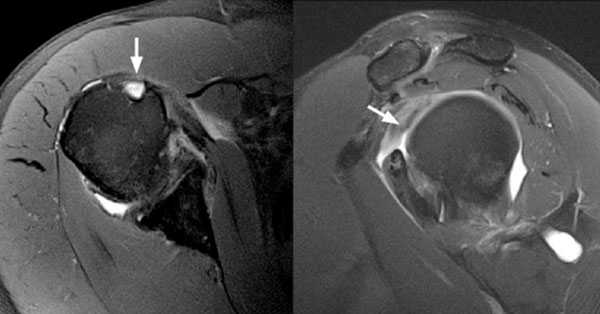

Для уточнения диагноза, определения степени повреждения подключают дополнительные методы обследования. Широко используется УЗИ, метод позволяет безошибочно определить полные разрывы. Для получения более точной информации о локализации повреждения, а также для визуализации небольших надрывов и внутрисуставных повреждений применяют МРТ.

Рис.3 МРТ-картина разрыва сухожилия длинной головки бицепса

МРТ. Данная разновидность лучевой диагностики обеспечивает получение детального изображения мягкотканных структур, позволяя, тем самым, выявить частичные, либо полные разделения сухожилий.